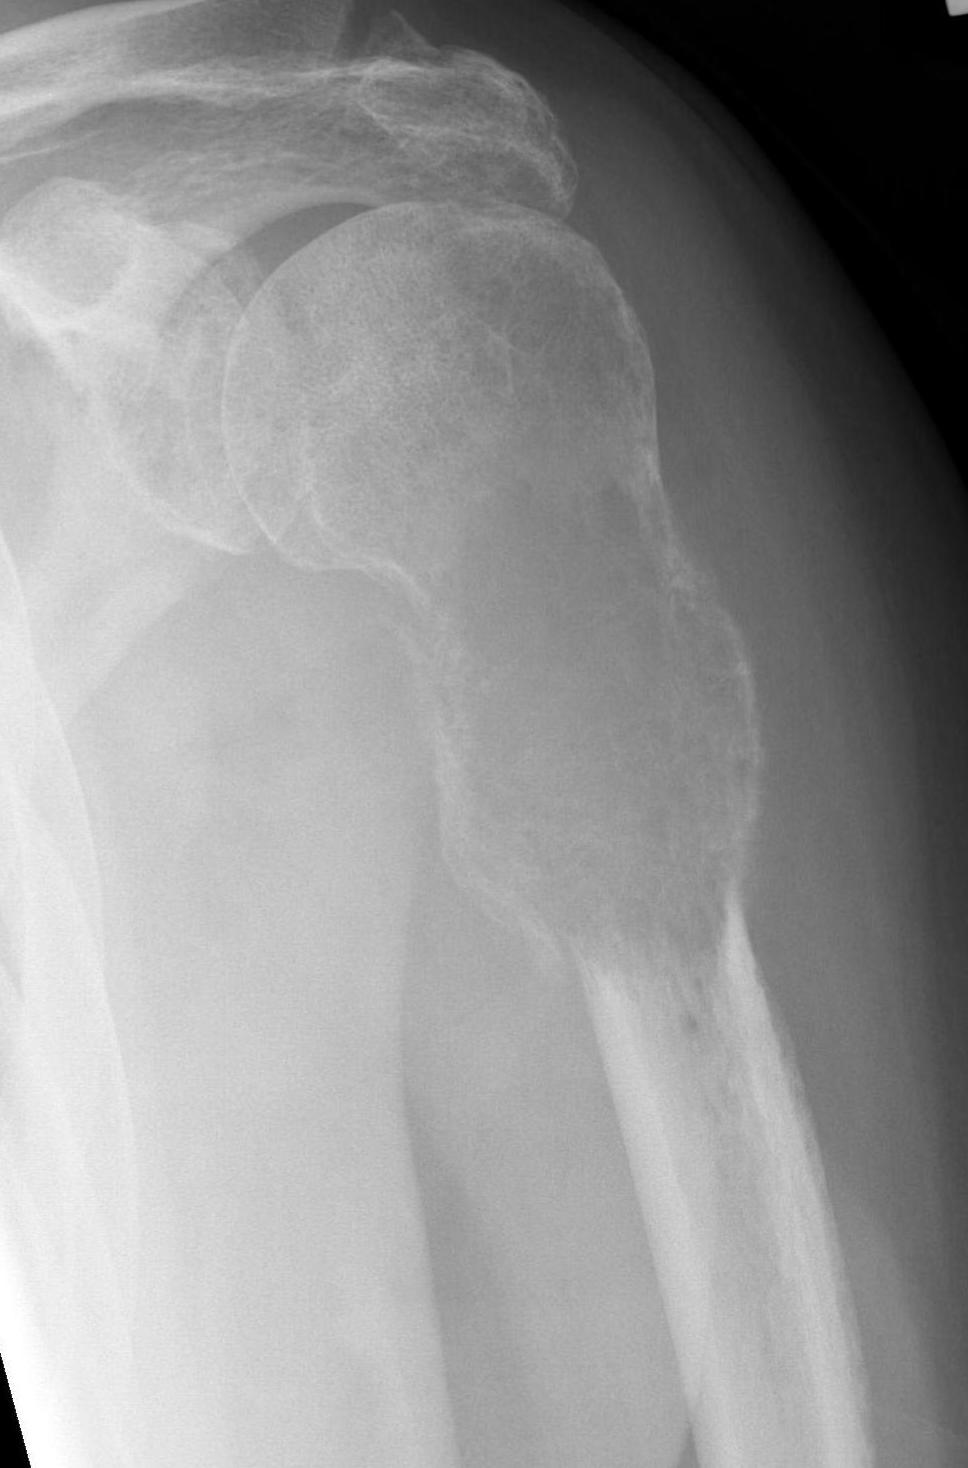

Proximal Humerus

Options

ORIF with plate +/- cement

IMN +/- cement

Tumour prosthesis

Results

Wu et al J Orthop Traumatol 2023

- 45 patients with proximal humerus metastasis

- IM nailing + cement versus plate

- lower blood loss and shorted hospital stay with IMN

- better pain relief with IMN